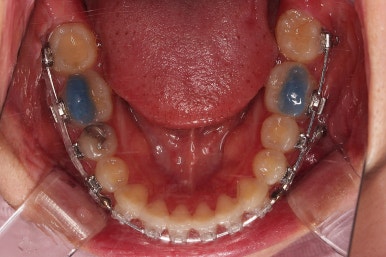

부산치아교정 이번 치료의 핵심인데요.

결손 부위에 미니스크류를 이용해서 뒤쪽 어금니들을 결손 부위로 앞으로 앞으로 계속 당겨줍니다.

얼굴모습에서의 중앙선도 지속저으로 체크하면서 한 쪽으로 치우침 없이 마무리를 해야 하고요.

틈새가 줄어들 때 까지 같은 작업을 반복합니다.

점점 틈새가 붙어가는게 보이죠?

계속 반복합니다.